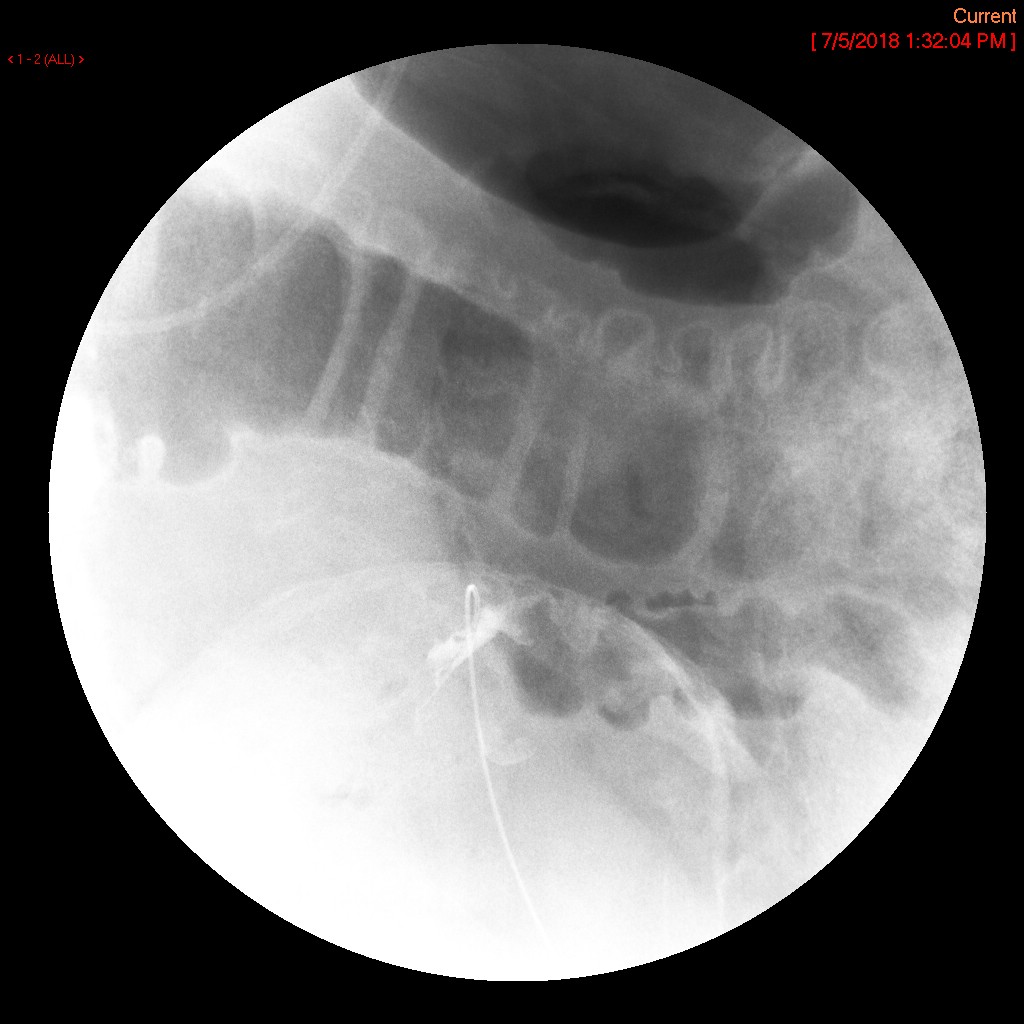

- Once you have the tube in the desired location, inject water soluble contrast material through the tube to verify location. Immediately after injection, obtain a spot image or do a screen capture showing final tube position.

- nasoduodenal

(key image 1)

- nasojejunal

(key image 2)